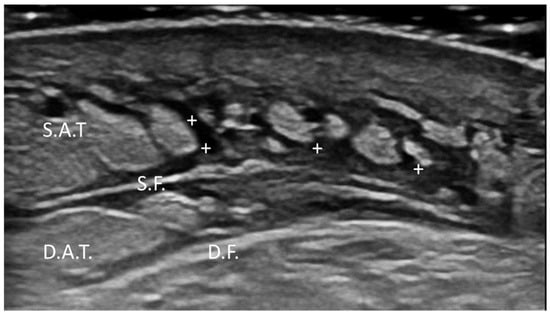

Lymphedema and Lipedema

- Pirri, C.; Pirri, N.; Ferraretto, C.; Bonaldo, L.; De Caro, R.; Masiero, S.; Stecco, C. Ultrasound Imaging of the Superficial and Deep Fasciae Thickness of Upper Limbs in Lymphedema Patients Versus Healthy Subjects. Diagnostics 2024, 14, 2697. [Google Scholar] [CrossRef] [PubMed] [PubMed Central]